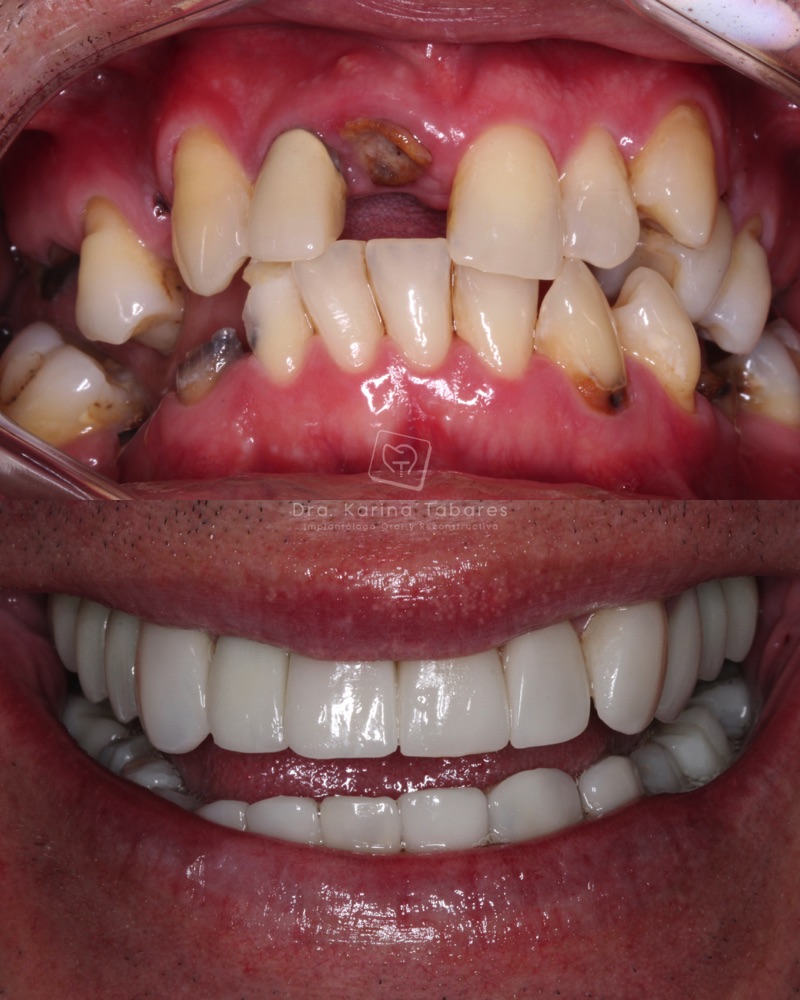

Antes y después

Cientos de pacientes han confiado en el equipo de la Dra. Karina Tabares y hoy comparten experiencias reales que han transformado sus vidas.